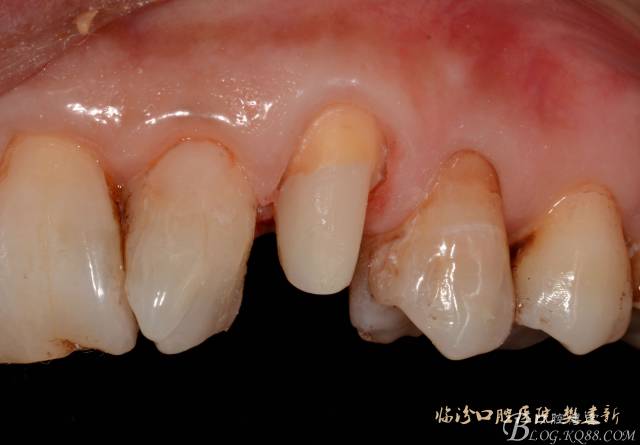

圖5 置纖維樁樹脂樁備牙后情況

圖6 23代臨時冠口內(nèi)照